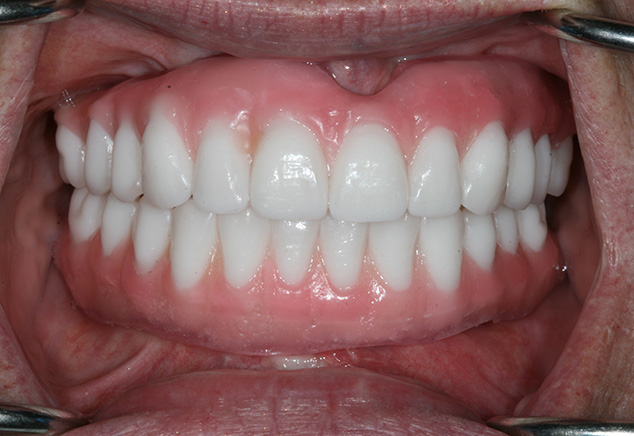

At the insertion appointment, the healing caps were removed and cleaned with Chlorhexidine. Figure 15 demonstrates the excellent healing of the soft tissue prior to insertion of the prosthesis. Once inserted, the esthetics, phonetics, and OVD of the prosthesis were confirmed. The occlusion was adjusted as needed. Screws were tightened to 15 Ncm, screw access openings were filled with Teflon tape to within 2mm of the surface, and a soft material such as Telio or Fermit was used to seal the access. A maxillary acrylic nightguard was fabricated to aid in protection of the occlusal surfaces from wear and to help reduce any parafunctional habits. The completed case is shown (Fig 15, Fig 16, Fig 17, Fig 18). At subsequent appointments, the prostheses were evaluated to determine if they needed to be removed to assess the soft tissue or if any contouring of the acrylic was necessary. Eventually the soft material used to close the access can be replaced with a hard composite material.